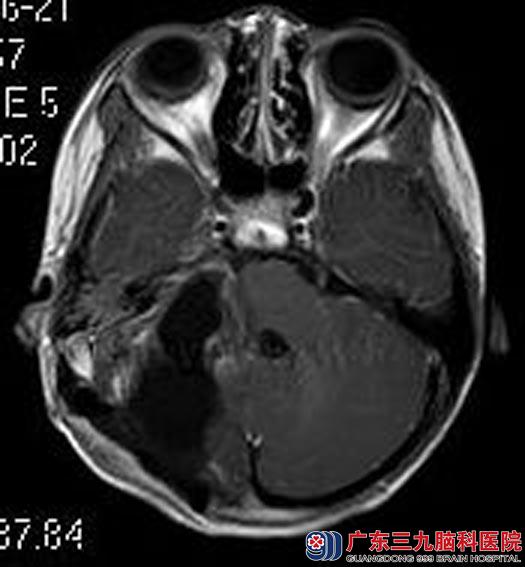

佳佳今年9岁,一个月突然出现了头痛,伴有恶心、呕吐,四肢抽搐三次。当地医院头颅CT检查提示右侧小脑半球占位。广东三九脑科医院进一步头颅MRI检查,结果提示:右侧桥小脑角区示一较大的团块状占位性病变,大小约4.05cm×2.96cm×3.69cm,小脑天幕强化,以右侧明显,脑干及四脑室稍受压,考虑髓母细胞瘤可能性大。